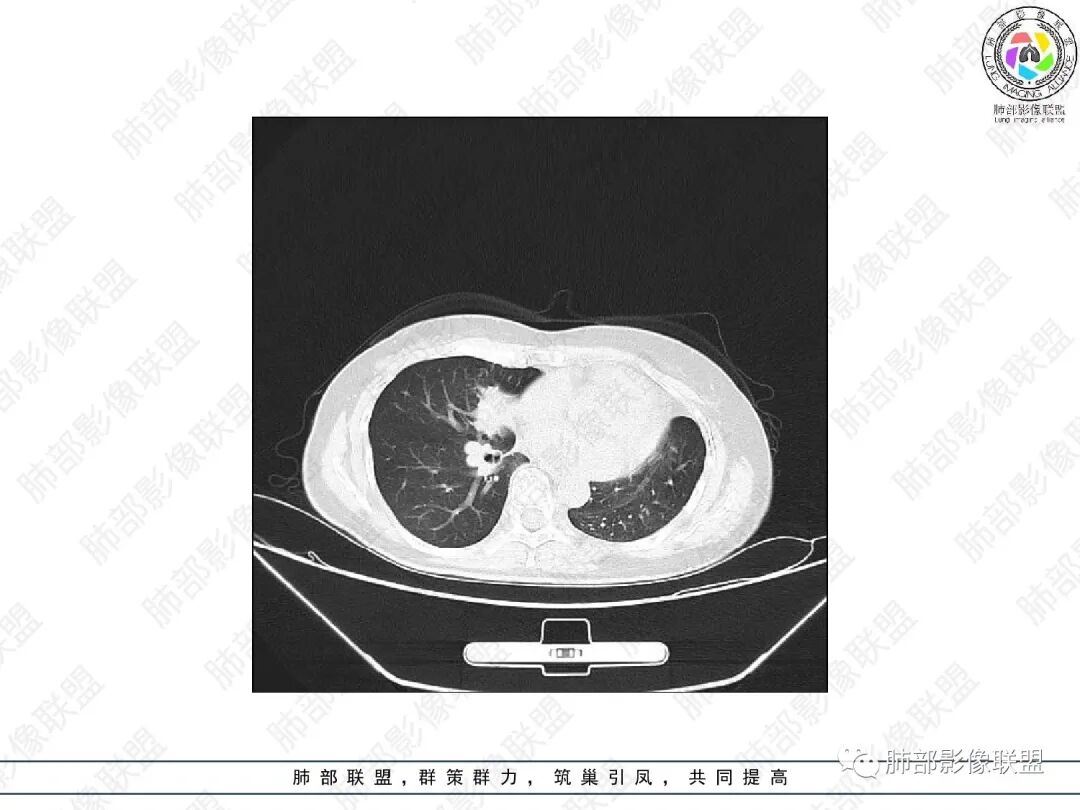

2.胸部CT:右肺上叶及中叶不规则块状影,沿支气管走行方向指套样影,支气阻塞湖嵌塞,腔内可见高密度影。灶周可见磨玻璃,外围见结节影及树芽征。左肺体积缩小,见不规则条索影、胸膜增厚,纵隔牵拉左移。

3.综合分析:结合患者病史及胸部CT主要鉴别ABPA(右肺上叶不规则块影,指套样顺延支气管方向,抗结核治疗1年,肺部病灶仍明显)及继发性肺结核TB(右肺上叶不规则肿块,其可见高密影,边缘模糊,周围卫星灶、树芽征,沿支气管爬行)。

完善气管镜及病理、检验结果(IgE显著增高)等支持ABPA诊断。且给予激素及伊曲康唑治疗后复查胸部CT提示病灶较前吸收,所以诊断明确。